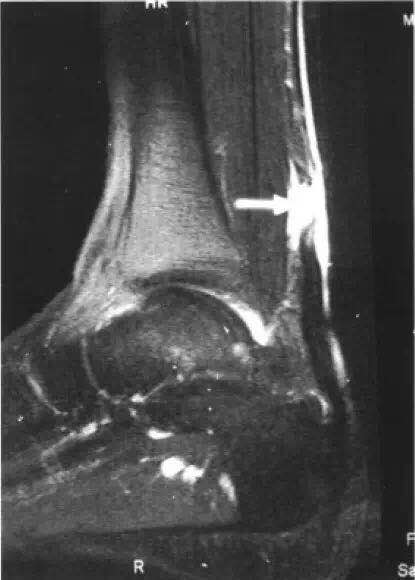

受伤后我们该如何判断跟腱是否受伤了,具体的受伤部位在哪儿?仅仅是部分撕裂还是完全断裂了?判断方法有以下几种:1、局部触摸:受伤局部压上去有疼痛感,如果是完全断了,局部可以摸到一个明显的凹陷;2、尝试足背向下活动动作,会发现疼痛伴乏力;3、受伤侧下肢不能落地行走;4、专科医生查体会发现Thompson征,亦即捏小腿三头肌试验(+);5、B超检查可明确损伤部位及损伤程度(但B超图像仅B超医师可以看懂);6、核磁共振(MRI)检查可清晰且直观地显示跟腱损伤的部位及程度(放射科医师、临床医师甚至患者都能看懂)。

跟腱断裂核磁共振表现